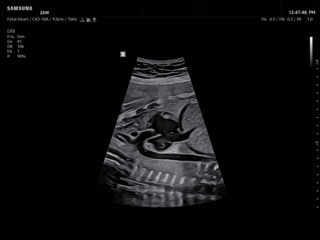

In the section "Оbsterics" of atlas the results of ultrasonic examinations of pregnant women with different durations of gestation are represented. Here you can see images of internally organs, cerebrum, cordis and the sex of the fetus, the sonograms of multiple pregnancy, the blood flow in placenta and umbilical cord, defects of fetal`s development, etc.